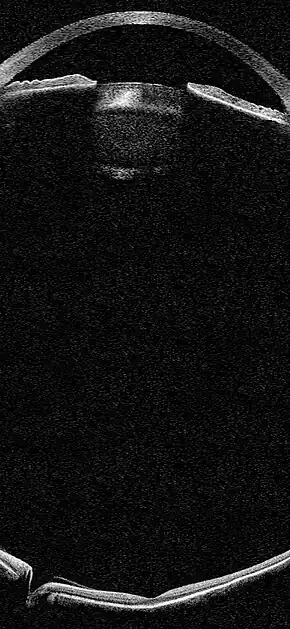

![]() Simulation of an OCT biomicroscopic image of the eye | |

OCT Biomicroscopy is the use of optical coherence tomography (OCT) in place of slit lamp biomicroscopy to examine the transparent axial tissues of the eye.[1] Traditionally, ophthalmic biomicroscopy has been completed with a slit lamp biomicroscope that uses slit beam illumination and an optical microscope to enable stereoscopic, magnified, cross-sectional views of transparent tissues in the eye, with or without the aid of an additional lens.[2] Like slit lamp biomicroscopy, OCT does not penetrate opaque tissues well but enables detailed, cross-sectional views of transparent tissues, often with greater detail than is possible with a slit lamp. Ultrasound biomicroscopy (UBM) is much better at imaging through opaque tissues since it uses high energy sound waves. Because of its limited depth of penetration, UBM's main use within ophthalmology has been to visualize anterior structures such as the angle and ciliary body. Both ultrasound and OCT biomicroscopy produce an objective image of ocular tissues from which measurements can be made. Unlike UBM, OCT biomicroscopy can image tissues with high axial resolution as far posteriorly as the choroid (Figure 1).